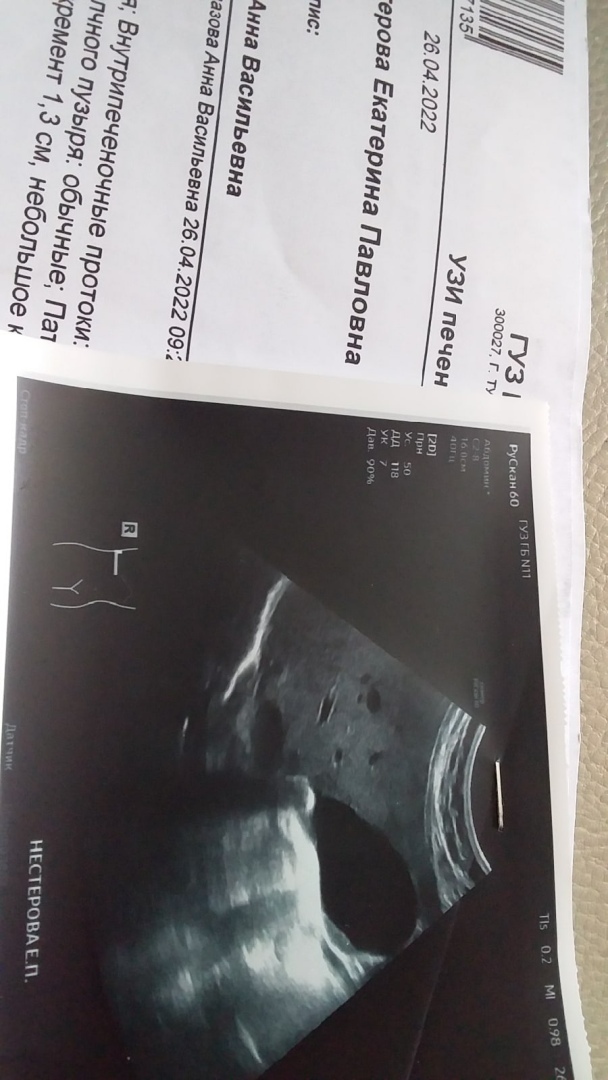

Начала принимать рассасывающие травы и аспаркам, который пью через трубочку (надо растолочь) 8 раз в день. Ну, а если не получится, то разорвется желчный пузырь, камень закрыл шейку поджелудочной железы, размер 1, 5 см.

Друг обещал сделать мне регистрацию, но это будет только 3 мая. Я из дома не выхожу, от страха ноги подкашиваются-мед полиса нет, никто не хочет принимать. А денег хватило бы на аренду, кредиты...

Да, если кто не знает, то поясню. Я замужем за русским, но у меня гражданство РБ (Белоруссия). И нет пенсии. Так уж получилось. Мне 62 года.